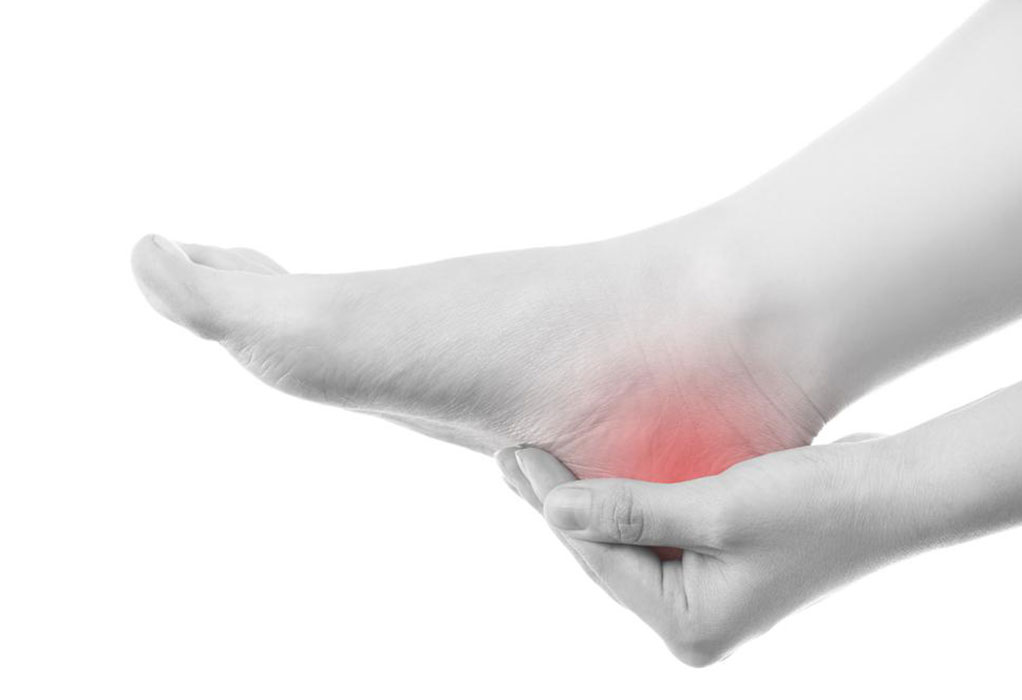

Gout is a type of arthritis or joint disorder. It causes severe pain accompanied by swelling and stiffness in the joints. Most commonly people are affected by gout on their toe. Once incurred gout could recur again. Over the long run, it damages the tissues in the affected area due to prolonged inflammation.